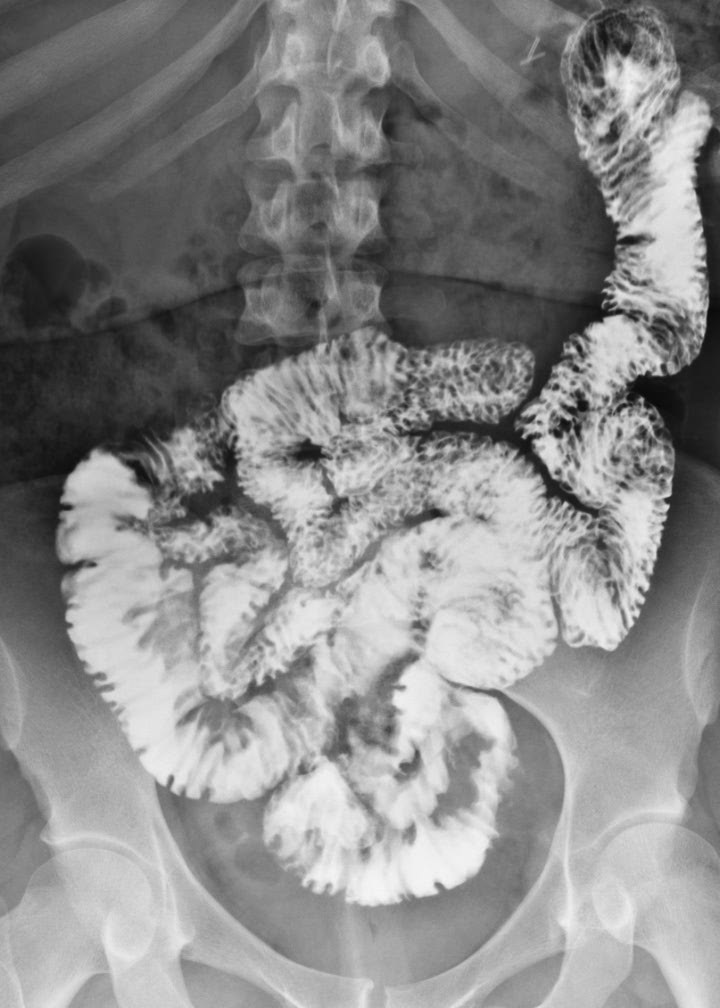

Images radiologique normale de intestin grele

baryte ( enteroclyse ) , a TDM et a echographie :

Generalement

intestin grele est

un tube musculaire de 6 a 8 m de longeur , a diametre

15/20mm avec des plies muqueuses en forme de valvules

conniventes avec anses relie au mesentere . Jejunum est

proximale et ilion est en distal , il se termine par valvule

ileocaecale et il est vascularisation par artere et veine

mesenterique superieure . Par la technique de opacification

baryte de l'intestin grele ( enteroclse ) , image

radiologique receillir sont : .les plies muqueuses intestinale avient une

epaissisement de 1,5-2mm ,aspect en feuille de fougere au

niveau jejunale , espace inter des plies est

moindre de 5mm et 15mm de ileon . Et a etat normale ,l'espace

inter-anse ne depasse pas 3mm et la largeur d'une anse

intestinale est 25mm

Images

radiologiques normales de intestin . Technique est

realise par une sonde

duodenal apres intiller150-200ml de baryte . C'est

proximale et ilion est en distal . Il se termine par valvule

ileocaecale |

Anse de l'intestin :

Espace inter-anse ne depasse pas 3mm et sa

largeur est 25mm |